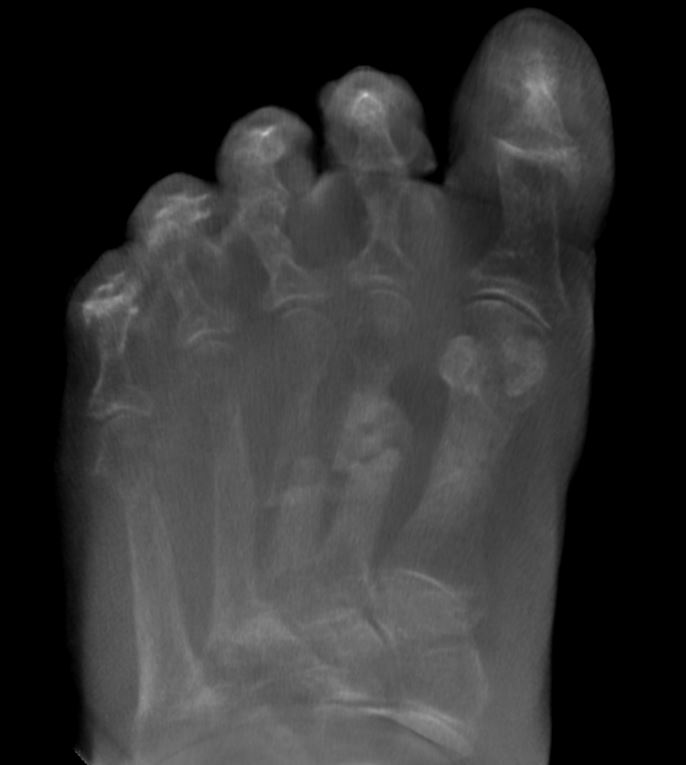

mehrzeitige Mittelfußserienfraktur bei schwerer Osteoporose